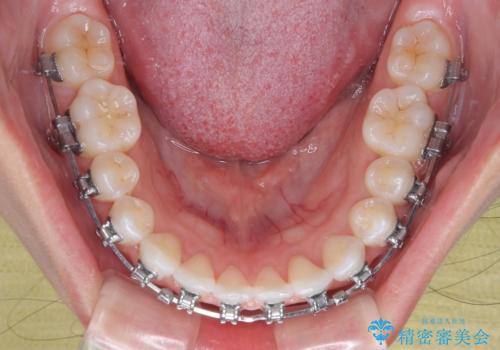

- 矯正装置

- メタルブラケット

- 上下前歯のデコボコを気にして来院された患者様です。

ワイヤー矯正でもマウスピース矯正でも可能でしたが、短期間で、自身の手を煩わせることなく治療を行いたいとのことで、ワイヤー装置にて矯正治療を行うこととしました。